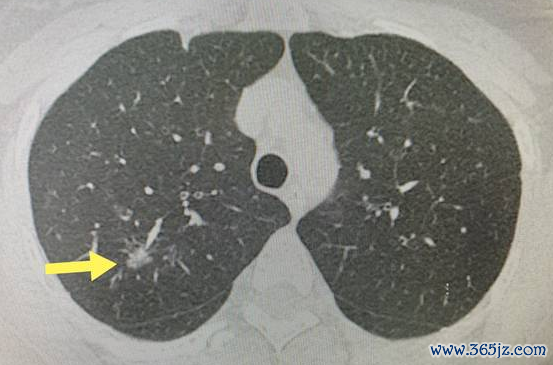

生活中很多人查出肺磨玻璃结节后就惶惶不可终日,大家不要谈到肺结节就色变,肺磨玻璃结节不一定都是恶性的,如下图,肺部炎症、过敏性病变、出血、纤维化等均可表现为肺磨玻璃影。比如外伤后检查出来的磨玻璃结节不要急于下结论及处理,这有可能是肺部的小血管破裂造成的。